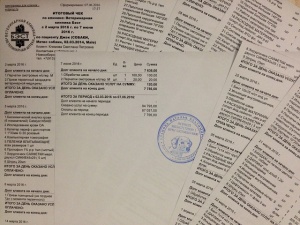

– предоплата за проведение компьютерной томографии правого скакательного сустава (КТ) врач Горшков Сергей Сергеевич, и операции (снятие пластины) хирург Козлов Евгений Матвеевич, клиника Бэст (чек 1, заключение КТ – документ 1, лист назначений – документ 1-1) – 5000 руб.;

– окончательная оплата за проведение компьютерной томографии правого скакательного сустава (КТ) врач Горшков Сергей Сергеевич, и операции (снятие пластины) хирург Козлов Евгений Матвеевич, клиника Бэст (чек 3, товарный чек 3, лист назначений – документ 3) – 7756 руб.;

Лист приема и назначений от 15.06.2016, итоговый чек за период 02.03.2016 - 07.06.2016.